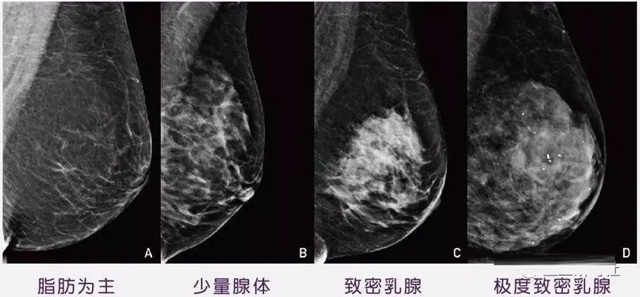

女性乳腺的自我檢查,特別是注意有小結(jié)節(jié),腫塊,乳頭有液體滲出情況,需要通過乳腺DR,X光線,磁共振等影像技術(shù)檢查。胸的大小跟乳腺癌沒多大關(guān)系,乳腺的密度大發(fā)病率高一些,胸小脂肪少致密性大。更容易乳腺癌。這個還不能通過自我檢查來確認(rèn)。致密乳腺組織看上去是白色或淺灰色需要通過乳腺X射線檢查。

乳腺X射線有輻射,40歲以下的女性沒有高危因素跟臨床特征,醫(yī)生都是不建議使用鉬靶檢查。乳腺超聲無創(chuàng)無輻射,對乳腺組織分辨率高??梢詫⑷橄倌[塊從致密型乳腺組織中輕松查出來,多普勒模式檢查乳腺及病變,超聲小于1厘米的病灶非腫塊性乳腺癌檢出率低。超聲檢查結(jié)果依賴醫(yī)生水平和經(jīng)驗,乳腺DR超聲推動乳腺超聲圖像的標(biāo)準(zhǔn)化,提高檢查的準(zhǔn)確率。對乳腺組織內(nèi)的細(xì)小鈣化灶, 從范圍、乳腺X射線形態(tài)以及分布特點上進(jìn)行定性診斷。造影劑增強型乳腺X線攝影靜脈注射碘化造影劑結(jié)合乳房X線攝影。磁共振MRI對乳腺癌研究的深入對軟組織具有較高的分辨率等特點,在臨床上被廣泛認(rèn)可。乳腺CT的探測器圍繞著乳房成像,無痛無擠壓,3D乳房圖像乳腺病灶的大小、數(shù)量、形狀、位置以及血管分布。一次掃描可創(chuàng)建多達(dá)兩千張投影圖像 。乳腺PET,適合普通人群和乳腺癌高危人群早期檢測,發(fā)現(xiàn)極早期微小病灶并明確定性。